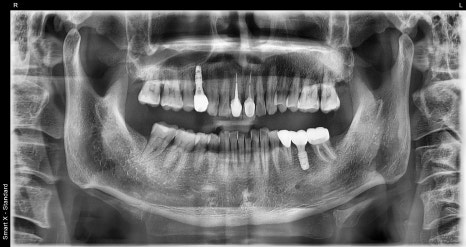

Left photo: Full panoramic X-ray taken after all root canal, implant, and prosthetic treatment were completed.

Right photo: Partial X-ray showing the treated tooth after root canal treatment and the implant well positioned.

➡ The tooth that received root canal treatment was properly filled all the way to the root with medication, and a prosthesis (crown) was placed well on top.

➡ The missing molar was also functionally restored with an implant, and the patient was satisfied with both chewing strength and comfort.